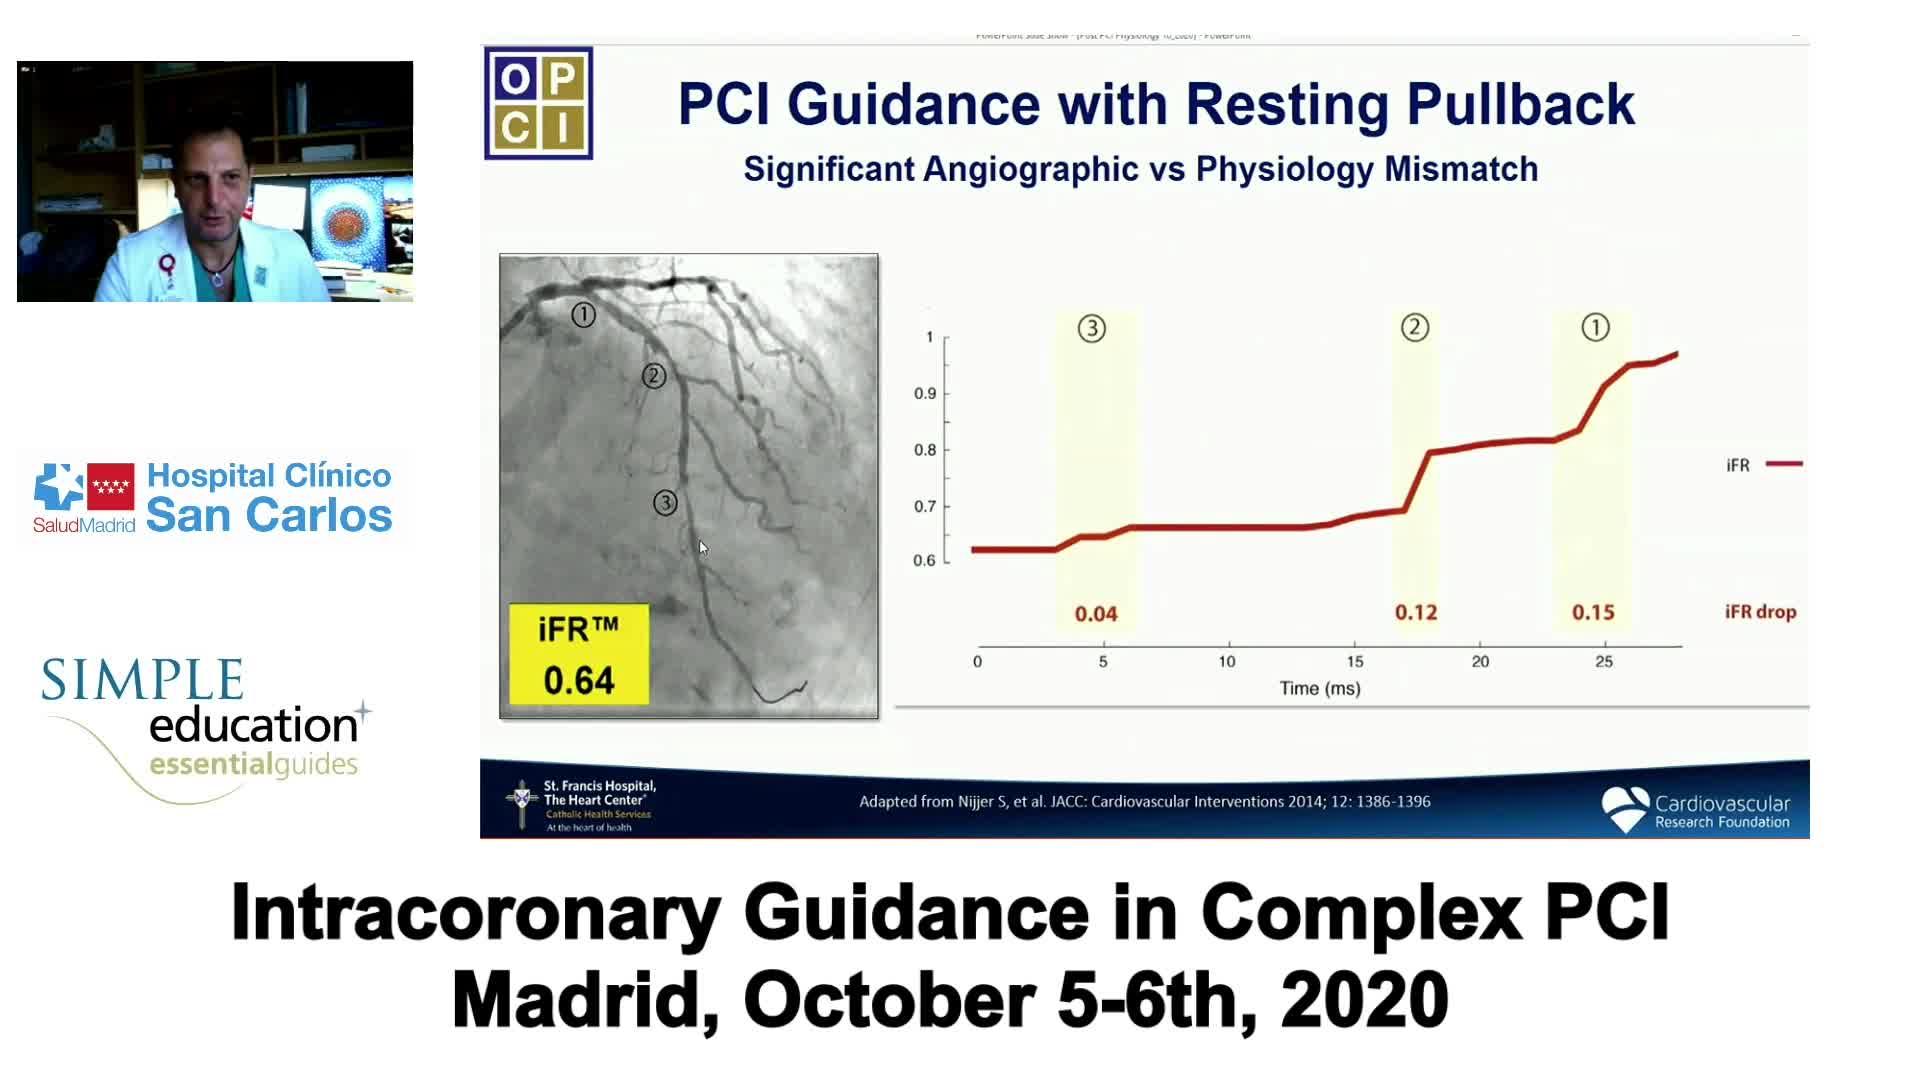

Essential steps for physiology-based PCI planning and guidance - Dr Allen Jeremias